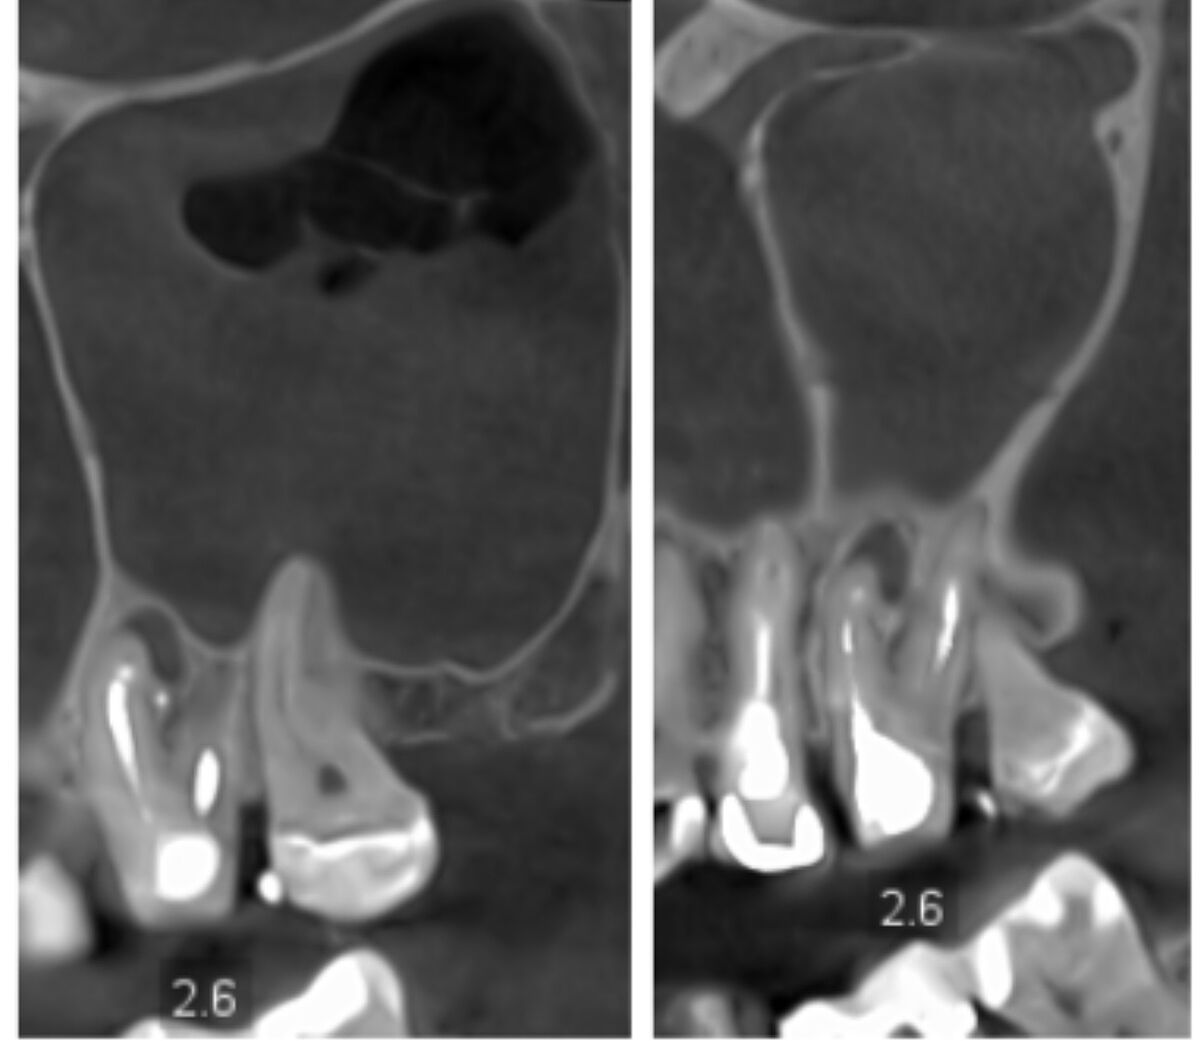

2.6 зуб: 3 кореня 4 канали (MB2); нерентгенконтрастна ортопедична конструкція, вкладка. Стан

ендодонтичного лікування: пломбувальний матеріал у каналі

простежується гомогенно, до верхівки, у каналах щічних коренів -гомогенно, не до верхівок. У верхівковій третині щічно-мезіального кореня визначається вогнище деструкції кісткової

овальної форми, неоднорідної структури (за рахунок фрагменту виведеної

пломбувальної маси), з чіткими, рівними межами, обідком остеосклерозу по периферії. розміром 3,65×5,5×4,05 мм (акс. *кор.* саг

ЗАКЛЮЧЕННЯ: КПКТ-ознаки лівобічного в/щелепного синуситу. Невиражених катаральних змін правої в/щелепної пазухи, носової порожнини. Кістовидної деструкції кісткової тканини альвеолярного відростка зубів 1.6, 2.6. Періапікальні зміни зуба 2.1.

Екструзії пломбувального матеріалу з коренів зубів 1.7, 1.5, 1.4, 3.5, 4.6, 4.7